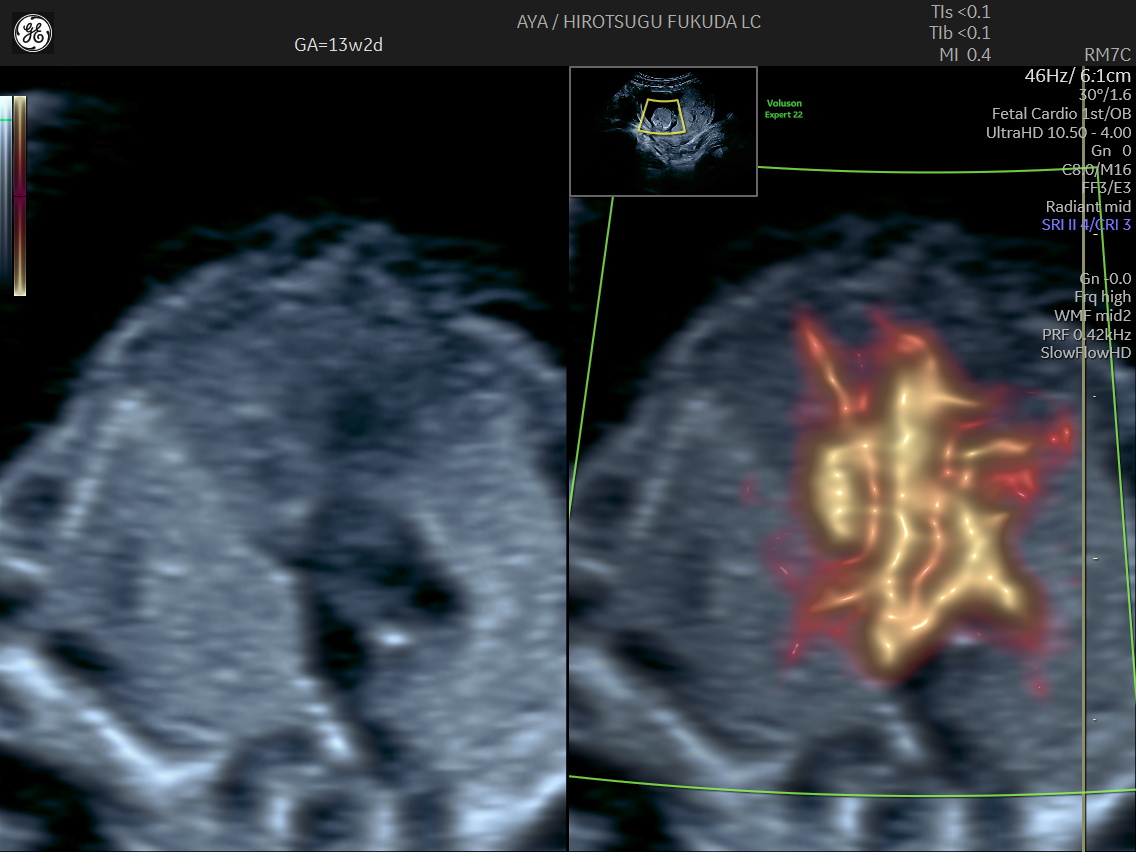

胎児心臓の初期評価

妊娠初期では観察が難しい胎児心臓についても、SlowflowHDを用いた血流描出を併用し、可能な範囲で流出路や大血管の位置関係の評価を行っています。

初期心臓評価の実際

下記は、妊娠初期における血流描出の一例です。初期心臓評価に関する取り組みについては、国際学術誌 Journal of Ultrasound in Medicine にも報告しています。

妊娠13週のslowflowHDによる心臓

妊娠13週の心疾患症例